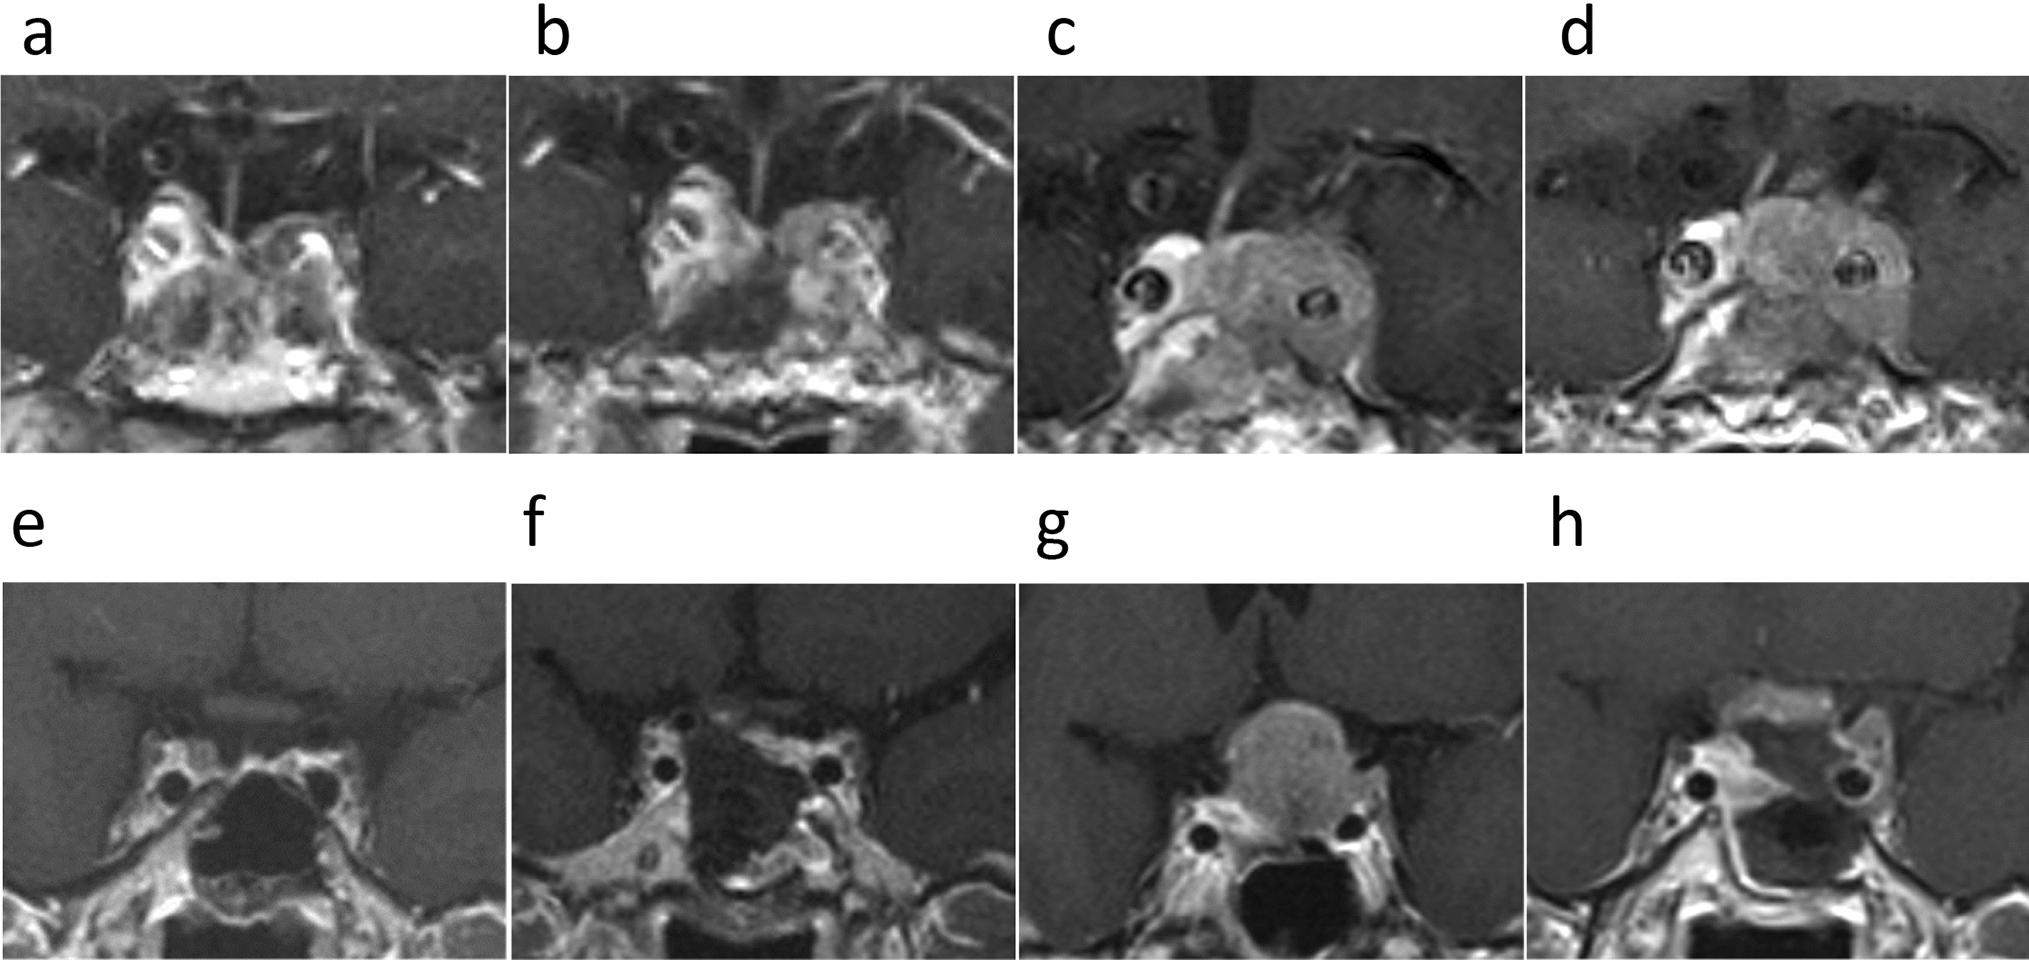

Huang S, Liu X, Zhu J, Sun Z, Chen Y, Yu H (2022) MR finding of extraventricular neurocytoma. J Coll Physicians Surg Pak 32:1478–1482. https://doi.org/10.29271/jcpsp.2022.11.1478

Sievers P, Stichel D, Schrimpf D, Sahm F, Koelsche C, Reuss DE, Wefers AK, Reinhardt A, Huang K, Ebrahimi A, Hou Y, Pajtler KW, Pfister SM, Hasselblatt M, Stummer W, Schick U, Hartmann C, Hagel C, Staszewski O, Reifenberger G, Beschorner R, Coras R, Keyvani K, Kohlhof P, Diomedi-Camassei F, Herold-Mende C, Giangaspero F, Rushing E, Giannini C, Korshunov A, Jones DTW, von Deimling A (2018) FGFR1:TACC1 fusion is a frequent event in molecularly defined extraventricular neurocytoma. Acta Neuropathol 136:293–302. https://doi.org/10.1007/s00401-018-1882-3